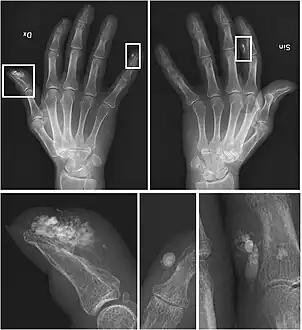

X-rays showing calcinosis in a woman with CREST syndrome

CREST causes thickening and tightening of the skin with deposition of calcific nodules ("calcinosis").